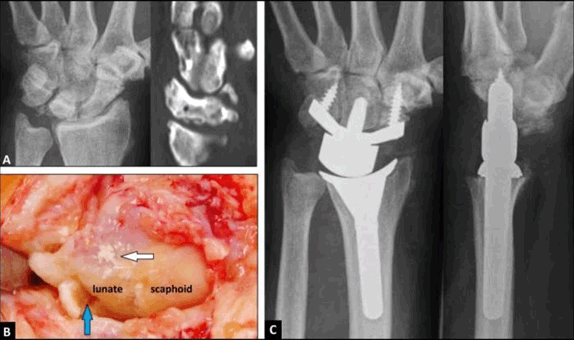

A 57-year-old male presented with increasing pain and swelling in his left wrist over a period of two years. There was no history of any trauma, and additionally, a systemic inflammatory disease was unknown to the patient. On examination, there were no inflammatory clinical signs locally, and all (non-)specific serum inflammatory markers (including uric acid) were not increased. With the use of radiographs and computed tomography (CT) scans, an advanced stage of Kienböck’s disease with peripheral stress fractures of the lunate bone and secondary arthritic signs of articular surface in the lunate fossa was primarily diagnosed (Figure 1A), that was confirmed by the radiologist as stage IIIB in magnetic resonance imaging. The motion-preserving total wrist arthroplasty (TWA) using the relatively new angle-stable Maestro™ Wrist Reconstructive System (WRS, Biomet, Warsaw, Indiana / USA) was indicated. Intraoperatively, there were multiple calcification deposits on and around the lunate, associated with the primarily diagnosed peripheral ‘stress fractures’ of the lunate (Figure 1B). Gouty monoarthritis of the wrist involving the lunate was confirmed on histological examination by the pathologist. Two years postoperatively, there was unchanged correct positioning of TWA without any signs of loosening or subsidence (Figure 1C). Pain in visual analogue score (0-10 points) and function in patient-rated wrist evaluation score (0–100 points) with 8 and 73 preoperatively had improved to 2 and 19. The patient reported that he would have the same procedure again if it would be necessary.

Figure 1(Case Presentation): (A) Posteroanterior radiograph and sagittal CT scan demonstrating primarily suggested advanced stage of Kienböck's disease with bony destruction, peripheral stress fractures and collapse of the lunate associated with secondary arthritic signs of the articular surface in the lunate fossa, (B) Clinical photograph intraoperatively showing synovial calcification deposits on and around the lunate (white arrow), and fracture of lunate (blue arrow), (C) Posteroanterior and lateral radiographs two years postoperatively showing correct positioning and alignment of TWA without any signs of loosening or subsidence.